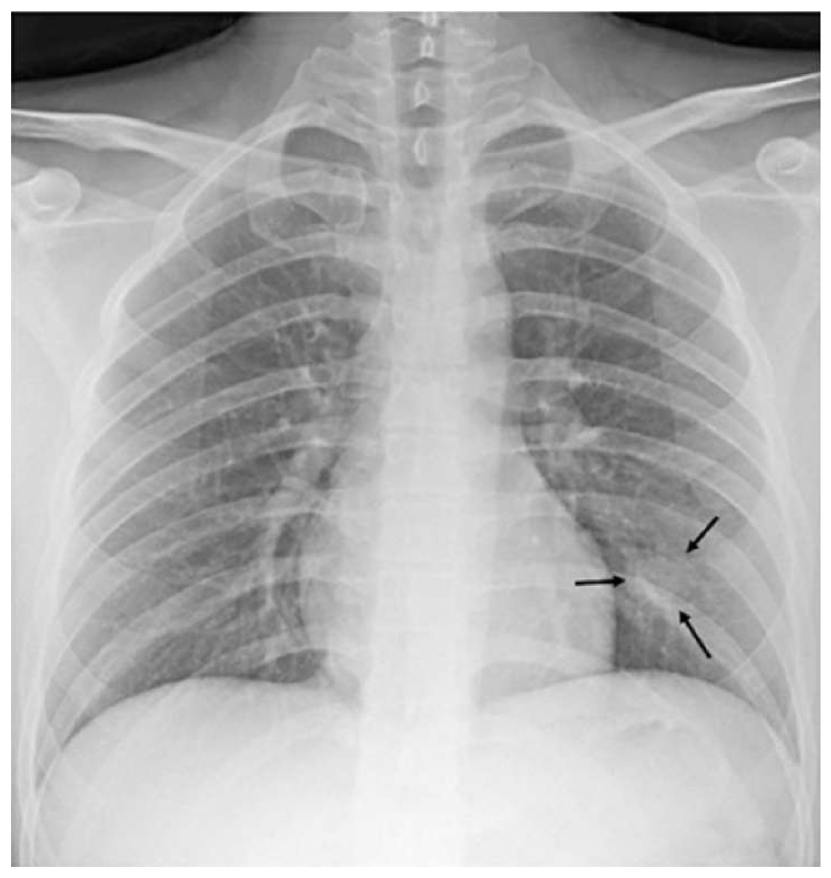

The most common imaging technique used as the first clinical step for chest-related diseases is CXR [26]. Hence, more CXRs could be collected publicly than CT images. A batch of randomly selected samples from the dataset with frontal view, also known as anteroposterior (AP) or posteroanterior (PA), is shown in Fig. 1.

Figure 1: Randomly selected frontal CXR images from different sources